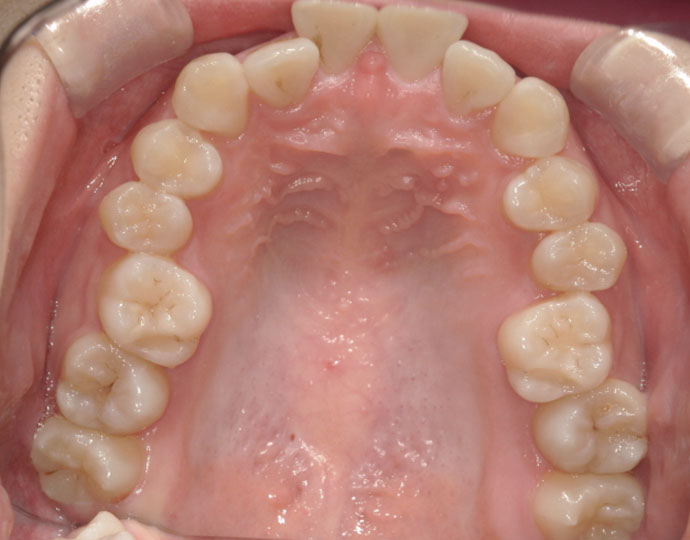

ワイヤー治療 叢生+上顎前突不正咬合 治療例

治療前

治療後

| 患者様 | 女性 19歳 |

| 主訴 | 歯並びと口元を綺麗にしたい。 |

| 診断 | 叢生歯列を伴う上顎前突不正咬合 |

| 治療方針 | 上顎左右第一小臼歯、下顎左右第二小臼歯の抜歯 |

| 治療に使用した装置 | セルフライゲーションブラケット インプラントアンカースクリュー×2 |

| 治療期間 | 2年6カ月 |

| 治療回数 | 24回 |

| 治療費(自費診療) | 880,000円(税込み) |